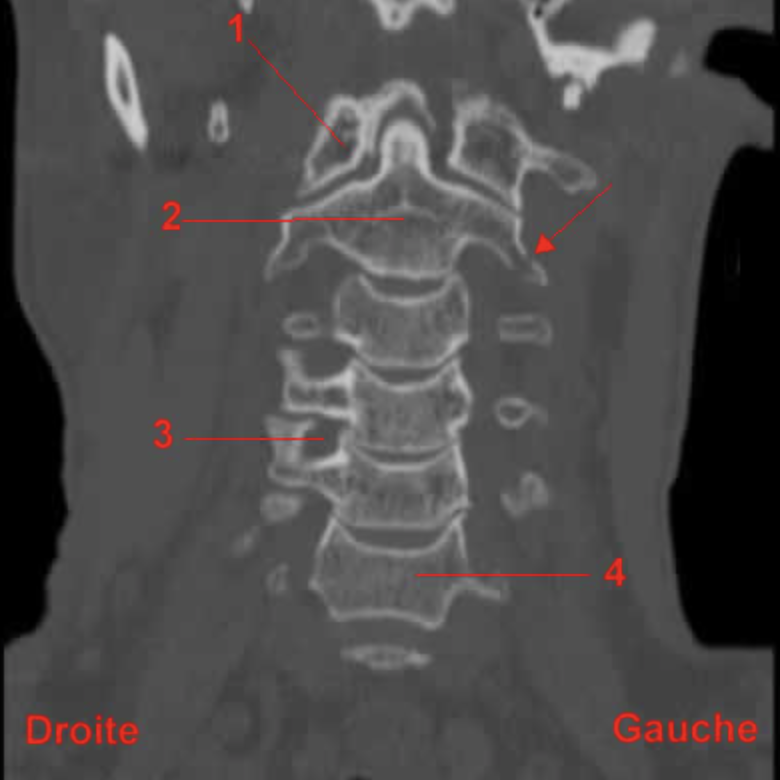

Ancien Responsable Matière Hypnos Posted May 4, 2020 Ancien Responsable Matière Posted May 4, 2020 le bord est convexe mais par la surface en elle même regarde, elles sont nettement concave vers le bas sur cette radio Quote

Solution YoungCalvitie Posted May 4, 2020 Solution Posted May 4, 2020 @Petit_Bateau @Paracelse bonjour ! Attention, le prof fait bien la distinction lorsqu'il décrit la partie centrale du spondyle et ses bords. En effet, il y a 2 choses bien distinctes: - Au centre du corps vertébral, la surface est concave. cela vaut pour sa face supérieure et sa face inférieure. comme l'a dit @Petit_Bateau, cela permet l'accueil du DIV. - Sur la périphérie du corps, en cervical, il y a la présence d'un système crochet/biseaux sur les parties latérales des corps. Si on regarde de face, le biseau sur le pourtour de la surface inférieure donne une concavité en haut. A l'imagerie au scanner (et non radiographie), on remarque plutôt la concavité centrale des spondyles. Pour se rendre compte du système crochets/biseaux, il faudrait plutôt rechercher un scanner de face comme celui-ci Alors on se rend compte que les surfaces antéro-latérales (ou postéro-latérales c'est indifférenciable sur ce cliché) comportent une concavité vers le haut, et c'est les crochets et les biseaux situés latéralement. En espérant avoir pu aider, N'hésitez pas si besoin Quote